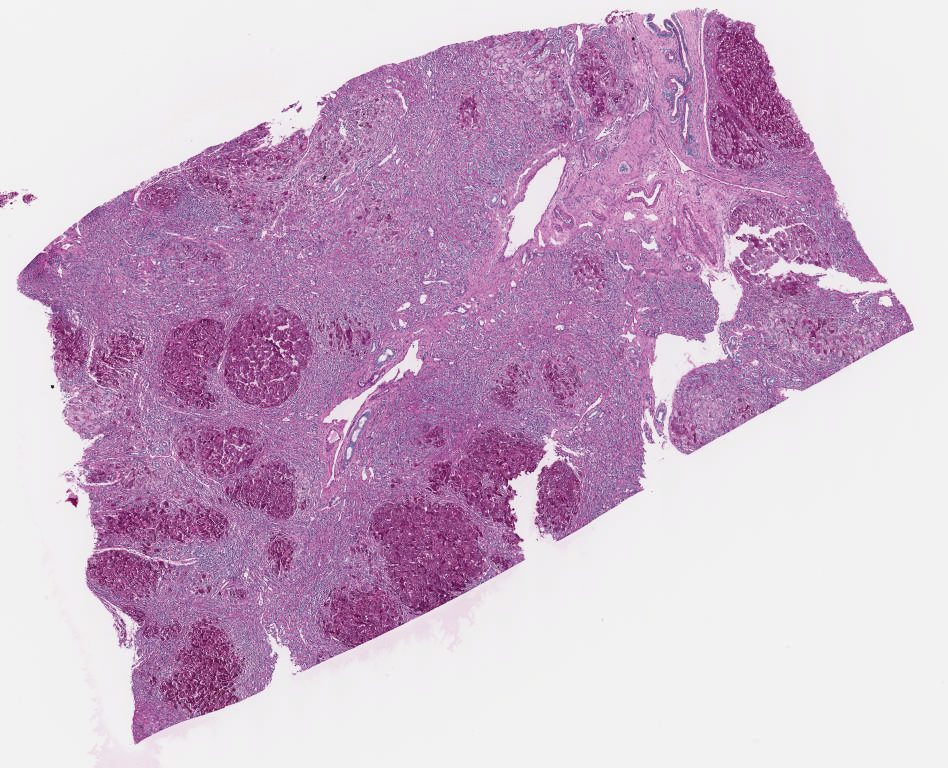

P - Jones.svs

27607 x 23168

@ 40X